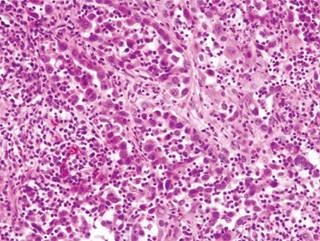

Dados los hallazgos y la alta sospecha de lesión tumoral, se realiza una biopsia guiada por TAC de la espinosa de T1 y del cuerpo vertebral de L2, siendo el resultado de estas biopsias negativo. Se decide programar una biopsia abierta en quirófano bajo control por escopía, siendo compatible el resultado en esta ocasión con el de un adenocarcinoma pulmonar (Figura 3).

Figura 3: Imagen de la anatomía patológica del paciente. Se observan células grandes con pleomorfismo celular y nuclear. El estudio inmunohistoquímico reveló que las células expresaban queratinas AE1-AE3, CAM 5.2 y sobreexpresión de p53, lo que sugiere un tumor primario pulmonar.